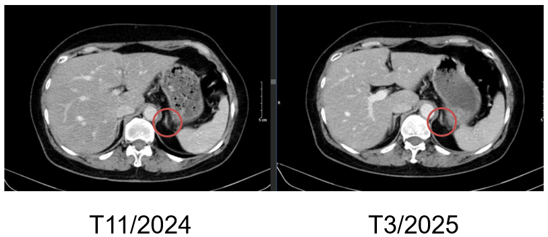

-  Chụp cắt lớp vi tính bụng: Theo dõi dày khu trú tuyến thượng thận trái tạo nốt đường kính khoảng 9mm

Hình 3. Hình ảnh chụp CT bụng trước điều trị: Nốt tuyến thượng thận trái

Hình 7. Hình ảnh chụp CT bụng trước và sau điều trị: Nốt tuyến thượng thận trái

- Chụp cắt lớp vi tính bụng: Theo dõi dày khu trú tuyến thượng thận trái tạo nốt đường kính khoảng 9mm (không thay đổi)

Hình 10. Hình ảnh chụp CT bụng sau điều trị: Nốt tuyến thượng thận trái

- Theo dõi đánh giá đáp ứng bằng cắt lớp vi tính ngực, bụng định kỳ, theo dõi sát tổn thương tuyến thượng thận.